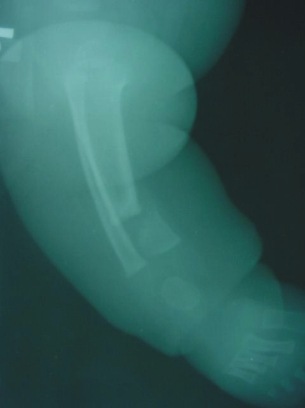

- Typ IV - (dysplastyczny) – najgorsze rokowanie, zagięcie przednio-boczne ze złamaniem i stawem rzekomym, z wrzecionowatym zwężeniem kości w obrębie stawu rzekomego, z całkowitym lub częściowym zamknięciem kanału szpikowego.

- śródszpikową stabilizację (gwoździe blokowane, pręty endera, TEN) Jeśli staw rzekomy jest blisko nasady do rozważenia jest założenie wszczepu śródszpikowego przezpiętowo. Zyska się w ten sposób dodatkową stabilność fragmentu dystalnego jednak kosztem późniejszych zaburzeń w obrębie stawu skokowego (Obu)